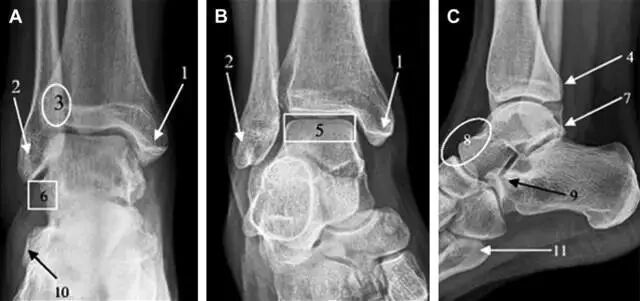

踝关节骨折的高危区(图 1)。

图 1 踝部探查模板。阅片时,需对踝关节的前后位片(A)、内旋转位片(B)侧位片(C)仔细阅读,逐一详细排查。上图中的骨折:1. 内踝骨折,2. 外踝骨折,3. 胫骨结节骨折,4. 胫骨后踝骨折,5. 距骨骨软骨骨折,6. 距骨外侧突骨折,7. 距骨后突骨折,8. 距骨舟骨关节背侧骨折,9. 跟骨前突骨折,10. 跟骨骨折嵌插入趾短伸肌,11. 第五跖骨底骨折

胫骨后踝骨折

涉及到三角韧带和外侧副韧带(LCL)的复杂性骨折常常不难发现,尤其是存在表面软组织肿胀时。然而,后胫腓韧带牵拉引起的胫骨后踝骨折则很难发现。这些骨折大小不一(图 2),却很重要,因为他们常与胫骨远端螺旋骨折有关,或者是三踝骨折的一部分。

图 2 胫骨后踝骨折。A 侧位片示来源于胫骨后踝的一个小骨折碎片(箭头),因踝部扭伤导致;B 另一位跖屈损伤的患者,侧位片示一个大骨折块(箭头)

胫骨结节骨折

Tillaux 骨折,是足外旋外展时,胫腓前韧带牵拉引起的一种胫骨结节撕脱性骨折。斜位片上可见典型表现(图 3)。

图 3 摔倒后胫骨结节骨折。A 正位片示一细小斜型骨折线(箭头);B 侧位片示正常;C 冠状位 CT 三维成像更清晰地显示了骨折线和骨折块大小(空箭头);D 矢状位 CT 多维重建图像示骨折位置(箭头)